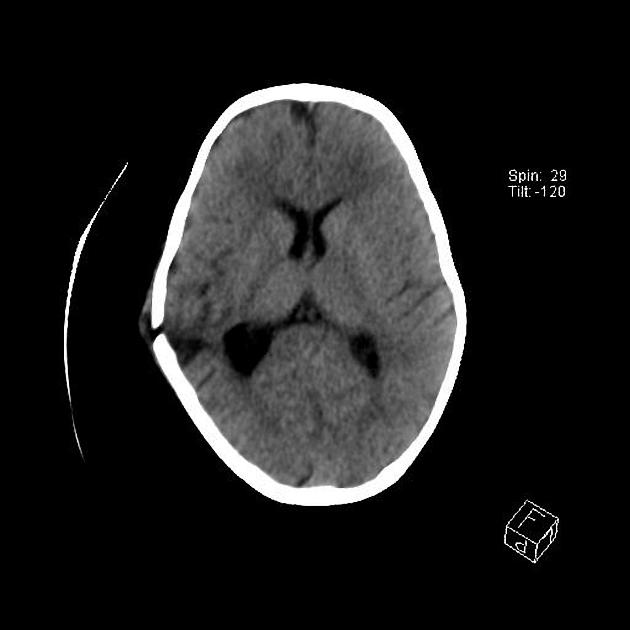

Example 3

Diagnosis

Skull fracture